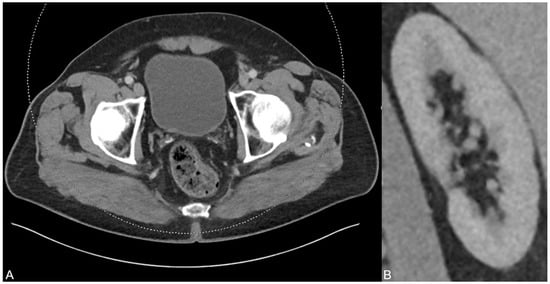

After six months and permanent therapy with potassium sodium hydrogen citrate, a control CT scan was performed showing no residues of the uric acid-based urine sedimentation in the bladder (A). In addition, no urinary stasis was present anymore (B), indicating the treatment success based on the dual-energy CT findings and analysis results.